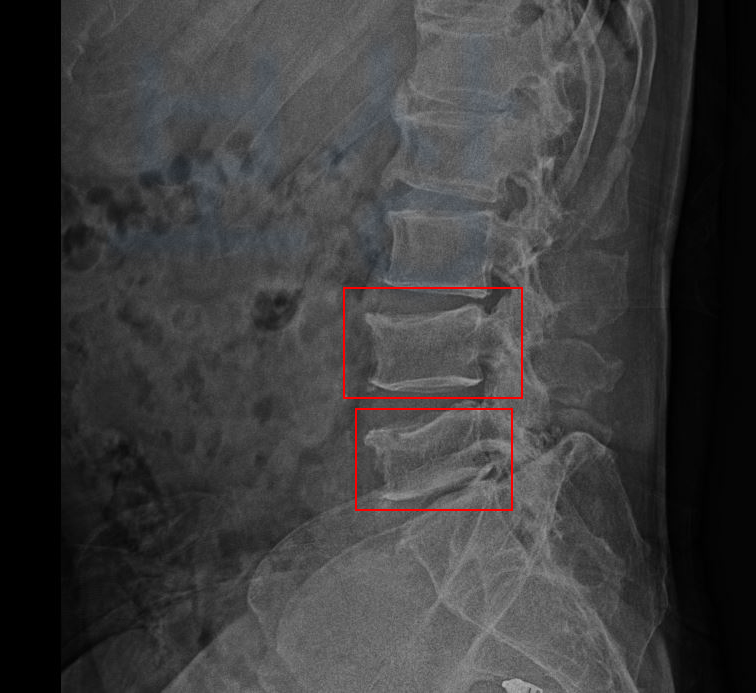

그 결과,

L4 부위의 골절 / L5 부위의 골절

진단을 받으셨습니다. L 은 Lumbar의 약자로서 4번, 5번은 척추체의 숫자를 의미합니다.

image

위 사진을 보시는 것처럼 요추 4번 5번이 압박골절되어 척추체의 전면이 주저앉은 모습 보이시죠? 요추 4번 5번 압박골절로 곽@@님은 TLSO 보조기를 착용하며 최소 12주간 입원 및 요양을 하셔야 했죠.